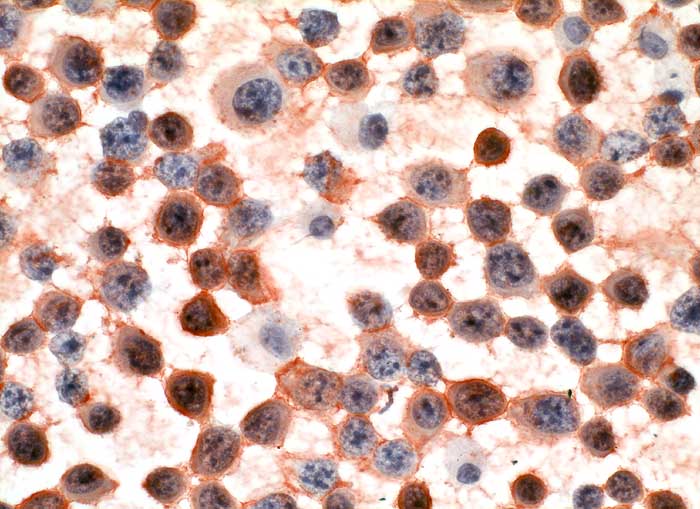

Pleuraerguss: die atypischen Plasmazellen sind positiv für den Plasmazellmarker CD138.

Immunzytochemisch sind die Tumorzellen negativ für den T-Linien-spezifischen Marker CD3 bei gleichzeitiger positiver interner Kontrolle in Form von eingestreuten kleinen reaktiven T-Zellen. Auch die Reaktion für den B-Zell-Marker CD20 ist negativ, dagegen reagieren sämtliche atypischen Zellen positiv für den Plasmazellmarker CD138 (Syndecan-1). Dieser Befund beweist zusammen mit dem zytomorphologischen Aspekt die Diagnose eines Plasmozytoms. Es dürfte sich mit hoher Wahrscheinlichkeit um ein extramedulläres Rezidiv des in einer früheren Knochenmarksbiopsie diagnostizierten, wenig differenzierten multiplen Myeloms (damals monoklonal positiv für Kappa-Leichtketten) handeln. Die Reaktion auf den Proliferationsmarker Ki-67 zeigt eine Positivität in ca. 80% der Tumorzellkerne, was auf eine ausgesprochen hohe proliferative Aktivität hinweist